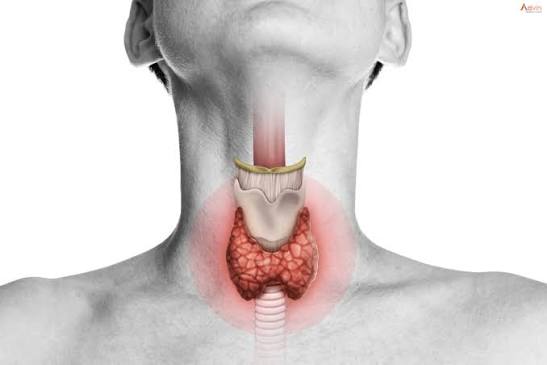

What is Thyroid Surgery?

Thyroid surgery, also called thyroidectomy, is a procedure to remove all or part of the thyroid gland, located at the base of the neck. The thyroid regulates metabolism through hormones like T3 and T4.